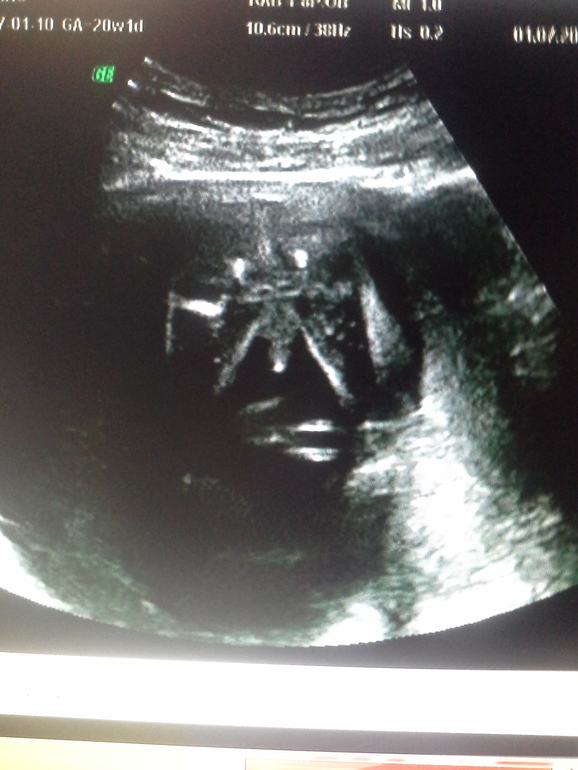

2.Вчера была на 2ом плановом узи. СУПЕР СУПЕР СУПЕР))) Кровь я не здавала так как на первом скриннинге риски были минимальны)

Первое что я увидела на экране это, простите, огроооомный писюн)